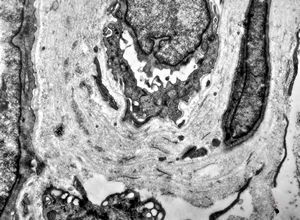

M, 48y. | multiplication of dermal perivascular basement membranes (unclassified myopathy)